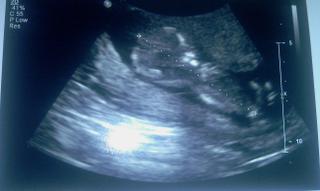

@renkita tak to je mi ľúto, že to tak dopadlo, viem ako sa cítiš, mňa môj doktor v 8. tt nastrašil, že nič nevidí, že gestačný vačok je prázdny, bola som úplne zúfalá, tak som písala Dr. Štelclovi do RF a zobral ma na utz, majú tam nejaký špeciálny a tam bolo všetko v poriadku, ale slzy mi tiekli cestou tam aj späť, ale späť boli od radosti, tak len pohodu a pokoj a toto bude posledný pokus ale úspešný 😉

@miminkad no to je super, že ste videli vačok aj s fetalnym polom...to sa dobre počúva... a hematon sa vstrebe, musí, len mu to trochu trvá, hnusák jeden...ale bude dobre.

@miminkad Moja, velmi sa tesim ... len takto pekne dalej ... inac baby, ze vy aku terminologiu pouzivate, ze fetalny pol a to je cooo??? 😕 😕 Opat budem o nieco mudrejsia 😉

@lenka_21 no ze je tam maly zarodocek plodu.super,ze si u cunderlika dopadla dobre 😉